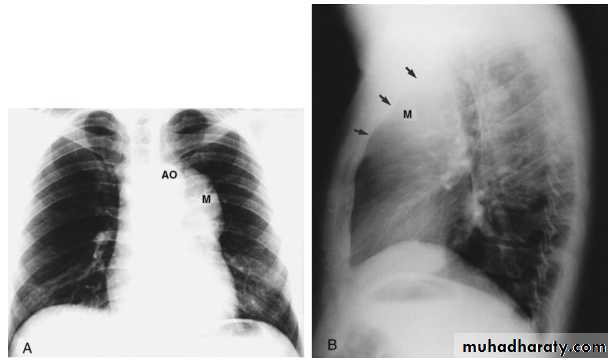

Pericardial fat pad. A, A soft tissue mass (arrows) is seen in the right cardiophrenic angle on the frontal chest x-ray. B, It also is seen in the anterior mediastinum on the lateral view. On this view, the anterior (A), middle (M), and posterior (P) portions of the mediastinum have been identified.